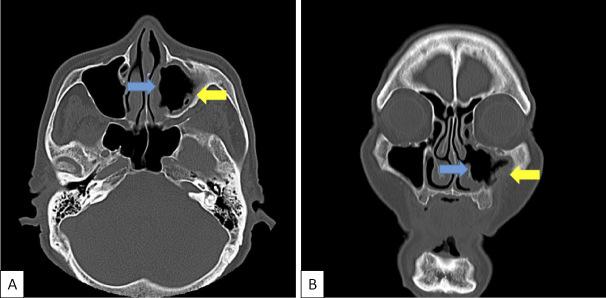

Post-trauma Mycobacterium avium chronic Rhinosinusitis Mimicking a Neoplasm.

https://cdn.ncbi.nlm.nih.gov/pmc/blobs/6dba/6443559/d2529fd44372/1349-7235-58-0761-g001.jpg